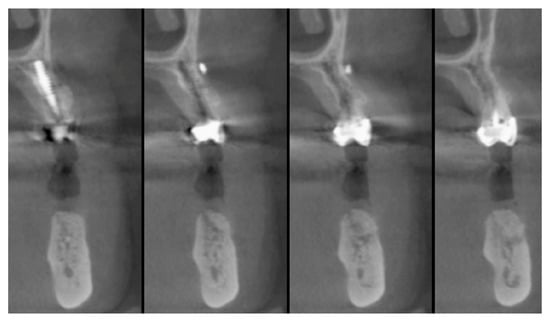

The vertical average defect was 9.16 mm, buccal lateral/palatal 7.0 mm, and mesio-distal 10.3 mm. The measurements were intraoperatively performed with a millimeter periodontal probe. The endodontic material mechanically cleaned before the tooth was placed inside the Tooth Transformer device. The endodontic material was removed using a drill bur with the attention to cut the canal in excess with the aim to remove all the cement. No surgical complications were registered. Pre and post-operative X-rays (section from CBCT) were collected from the same case (Figure 1, Figure 2, Figure 3 and Figure 4). After four months, 13 histological and histomorphometrical evaluations were performed (Figure 5). The Bone Volume/Total Volume average (BV%) was 41.47 (S.D. ± 11.51), the Residual Graft/Total Volume average (Graft%) was 16.60 (S.D. ± 7.09), and the Vital Bone/Total Bone average (VB%) was 21.89 (S.D. ± 9.72). No extraneous material (gutta-percha or cement) was detected in all samples (Table 3).

Applsci 09 05396 g002

Figure 3. The cbct section in zone 36, two months after the Guided Bone Regeneration (GBR). The defect was completely filled using the endodontical treated elements site 3.5 and 3.6 (Italian teeth numeration).

Applsci 09 05396 g003

Figure 4. The cbct section in zone 36 after the implants healing, six months after the GBR.